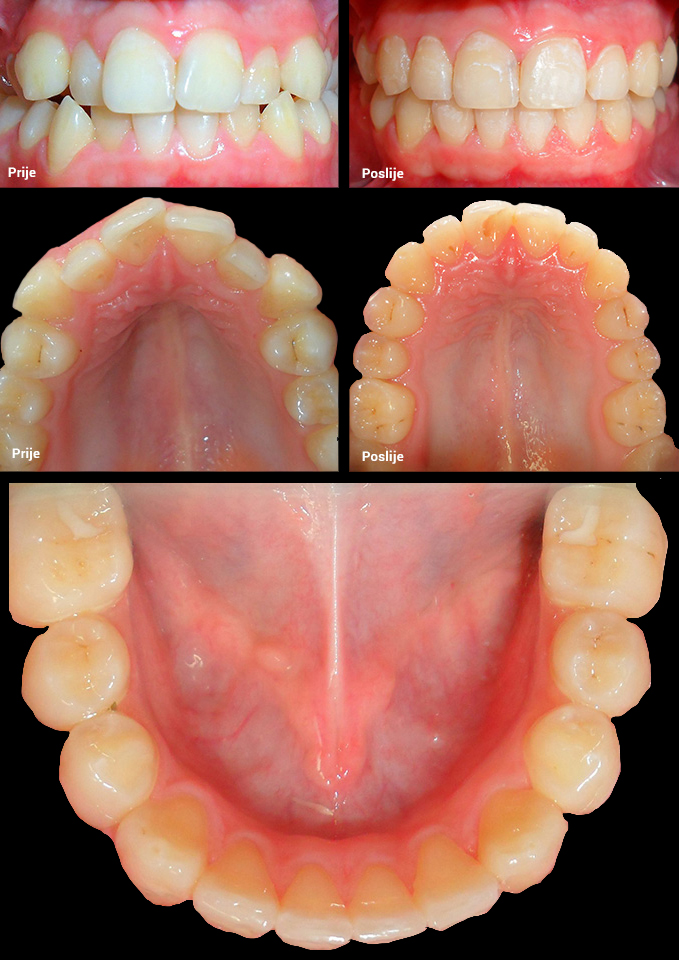

O našoj kvaliteti najbolje govore naši rezultati!

Centar za ortodonciju Petra Džapo